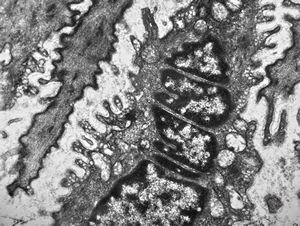

normal mucosa - stomach - parietal cell